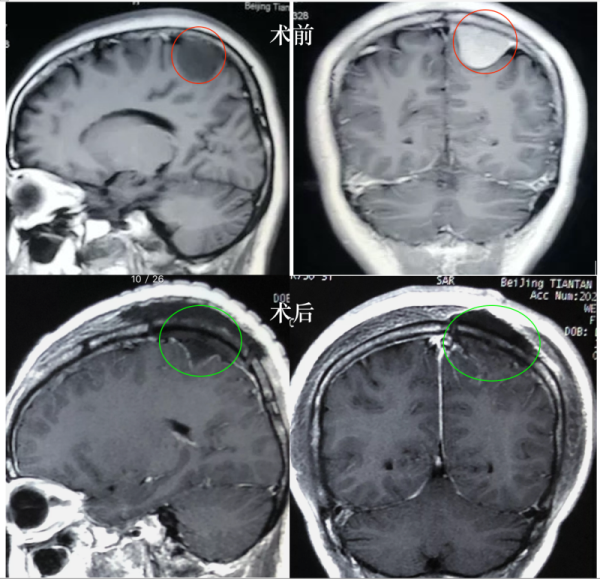

35歲女士,2020年2月在A醫(yī)院確診為左頂凸面占位腦膜瘤,大小約3cm,6月實(shí)行全切切除。病理分析為who1-2級(jí),Ki67為15%,建議咨詢放療專家。

總結(jié):WHO病理結(jié)果本身也受病理醫(yī)師、檢測(cè)方法的影響,甚至術(shù)者所取標(biāo)本組織的差異也會(huì)決定病理結(jié)果的不一致,臨床中這樣的情形偶爾可見(jiàn)。在該病例中,凸面腦膜瘤靠近運(yùn)動(dòng)功能區(qū),手術(shù)全切,WHO分級(jí)及Ki67指數(shù)不同醫(yī)院結(jié)果不一樣,患者病理提示I級(jí)或I-II級(jí),Ki67指數(shù)5%-15%,放療或不放療都有潛在“收益和風(fēng)險(xiǎn)”。根據(jù)在德的經(jīng)驗(yàn)和治療指南,結(jié)合病人年齡、靠近功能區(qū)、影像特點(diǎn)、手術(shù)全切、病理結(jié)果及術(shù)后無(wú)明顯功能障礙,建議密切觀察MR及隨訪,可暫不放療,如果腫瘤復(fù)發(fā),病情允許,建議再次手術(shù)治療。病人遇到這樣的情況時(shí),多咨詢是對(duì)的,建議能較終明確病理結(jié)果,若情況允許可以再取標(biāo)本組織重做病理切片。同時(shí)也是建議選擇較了解患者病情的好的主管醫(yī)師就診,根據(jù)病人情況綜合決定治療方案,不同神經(jīng)外科醫(yī)師、放療科決策者的經(jīng)驗(yàn)和認(rèn)識(shí)不同、病患的需求不同,都會(huì)造成治療建議的差異,況且很多治療方案都是有潛在的益處和風(fēng)險(xiǎn),病人個(gè)體也具有很大差異,對(duì)于很多尚有爭(zhēng)議的領(lǐng)域,醫(yī)學(xué)上也沒(méi)有“統(tǒng)一、正確”的方案,很多時(shí)候醫(yī)者也只能給出醫(yī)學(xué)角度的建議。